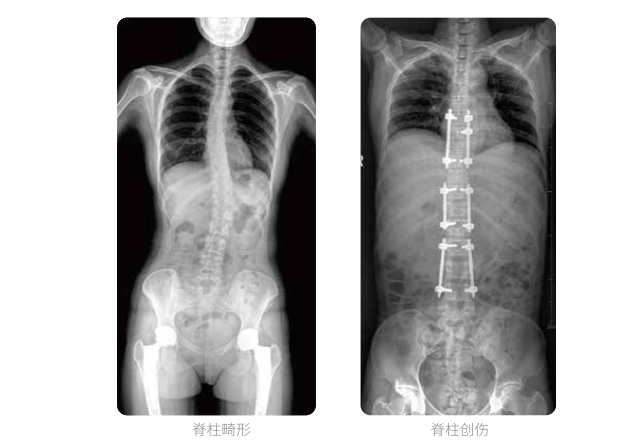

近年來,脊柱及下肢畸形的患者較多,多發于青少年的脊柱側彎畸形,骨性關節炎、風濕性關節炎以及雙下肢畸形如膝關節內外翻、X型O型腿等也是骨科常見病。并且發病率呈現逐年升高的趨勢,常常累及下肢髖、膝、踝3個負重關節,影響患者生活,甚至喪失工作能力。

在脊柱及下肢畸形的臨床治療過程中,一般需要進行矯正手術治療,在對其進行手術前后,均需要拍攝X光片以便分析病情、明確診斷和觀察治療效果。常規DR拍攝面積有限,最大規格僅有43cm,但成人男性全脊柱長度平均為70-75cm,女性為66-70cm,而雙下肢更長。普愛醫療PLX8600動態DR的43cm*86cm超大有效視野,可一次性拍攝全脊柱、雙下肢的影像視野。

常規DR攝片技術不能一次性拍攝出完整的全脊柱或雙下肢的X光影像。全脊柱的拍攝需要分別拍攝頸椎、胸椎、腰椎的X光片,雖然能夠觀察到局部的側彎情況,但不能觀察到三者之間的連續性,這就增加了這類疾病的診治難度。

普愛醫療動態數字化X線攝影(動態DR)擁有43cm*86cm超大有效視野,使全脊柱及雙下肢能夠得到完整清晰的成像,為臨床在脊柱側彎畸形和下肢骨關節病變診斷、治療方案制定及治療后復查提供精準的測量。

全脊柱臨床影像

普愛醫療動態數字化X線攝影(動態DR)可以使整個脊柱一次成像,直觀顯示脊柱的整體形態以及側彎部位,評價側彎的病理程度,全面了解脊柱各個階段的生理曲度及椎間關節連接的關系,避免了常規脊柱攝影對整個脊柱曲度的影響。為脊柱側彎的診斷治療提供了重要的影像學依據。